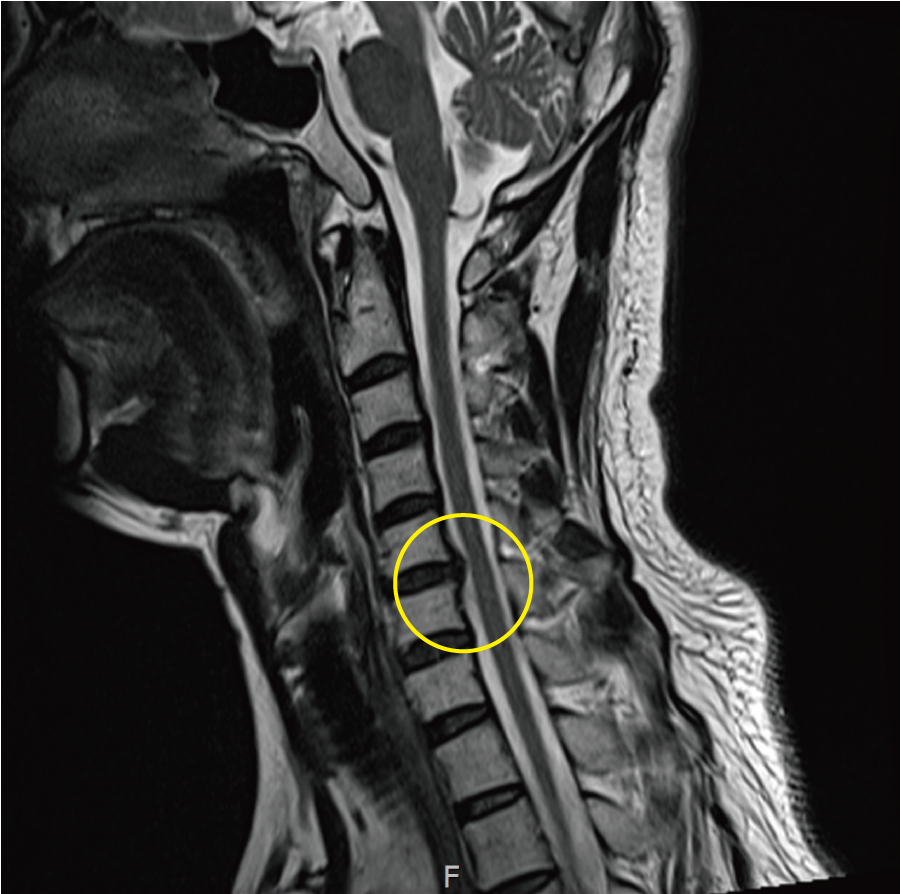

넷째, 목디스크로 인한 근력 약화가 생길 수 있습니다. 목과 팔의 근육이 약해지면 물건을 잡는 것이 힘들어지고, 반복적인 움직임이 어려워질 수 있습니다. 이는 특히 직업적인 활동에 큰 영향을 미칠 수 있습니다.

다섯째, 두통 증상이 발생할 수 있습니다. 목 디스크로 인해 목의 근육이 긴장하게 되면, 이로 인해 두통이 유발될 수 있습니다. 특히 스트레스나 긴장 상태에서는 두통이 더욱 심해질 수 있습니다.

목디스크 증상이 심해지기 전에 정기적인 건강 검진을 통해 상태를 점검하는 것이 좋습니다. 특히 목과 관련된 문제가 있을 경우 전문의와 상담하여 필요할 경우 물리치료나 약물 치료를 받는 것이 중요합니다.

전문가의 도움을 통해 적절한 치료 방법을 찾고, 유지 관리하는 것은 목디스크뿐만 아니라 전반적인 건강을 지키는 데 큰 도움이 될 것입니다. 자가 진단이나 자가 치료보다 전문의와 상담하는 것이 가장 바람직합니다.